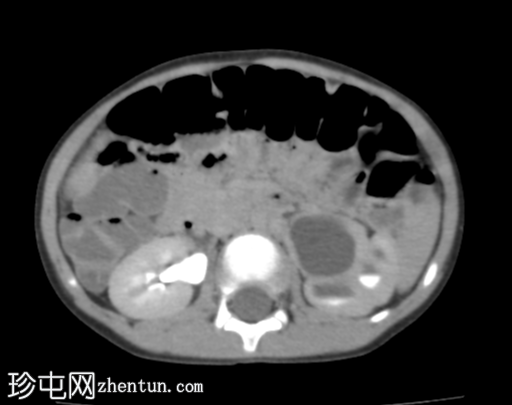

肾轴位

实质期

左侧肾盂肾盏系统中度扩张;但未见明确的放射性结石。

右肾未见异常。

影像

学表现最可能为左侧肾盂输尿管连接部梗阻。